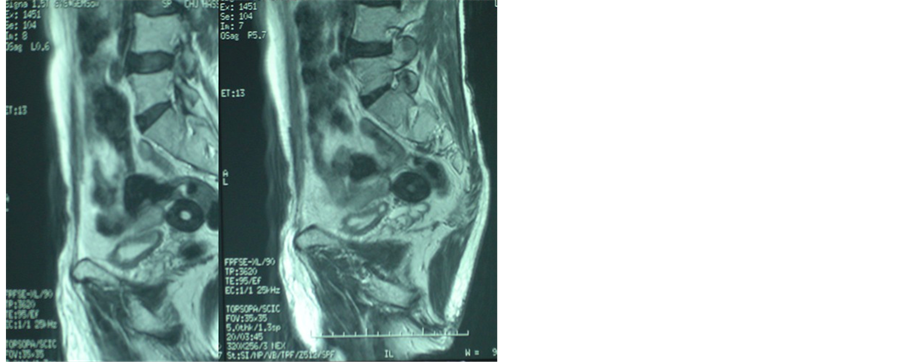

We report the case of a 64-year-old man with no remarkable medical history who presented with six months recurrent hematuria, chronic pelvic pain syndrome (CPPS) and inconstant symptoms of tenesmus. Routine blood tests, including PSA, testosterone and prolactin levels, were normal. Transrectal ultrasonography (TRUS) showed a hyperechoic localized tumor in contact of the right seminal vesicle and a posterior enhancement of central calcification (Figure 1). Computerized tomography scan (CT) and magnetic resonance imaging (MRI) demonstrated an oval well circumscribed retrovesical soft tissue lesion measuring 3.9 × 3.7 × 4 cms with a central negative density (−40.92 UH) and positive peripheral density (+48.17 UH) without enhancement after injection of contrast product. This well-circumscribed egg-shaped lesion seems to be in contact with the right seminal vesicle (Figure 2 and Figure 3).

Figure 3. MRI: sagittal image of the pelvis revealing a well- circumscribed egg-shaped lésion measuring 3.9 × 3.7 × 4 cms cm with central calcifications.